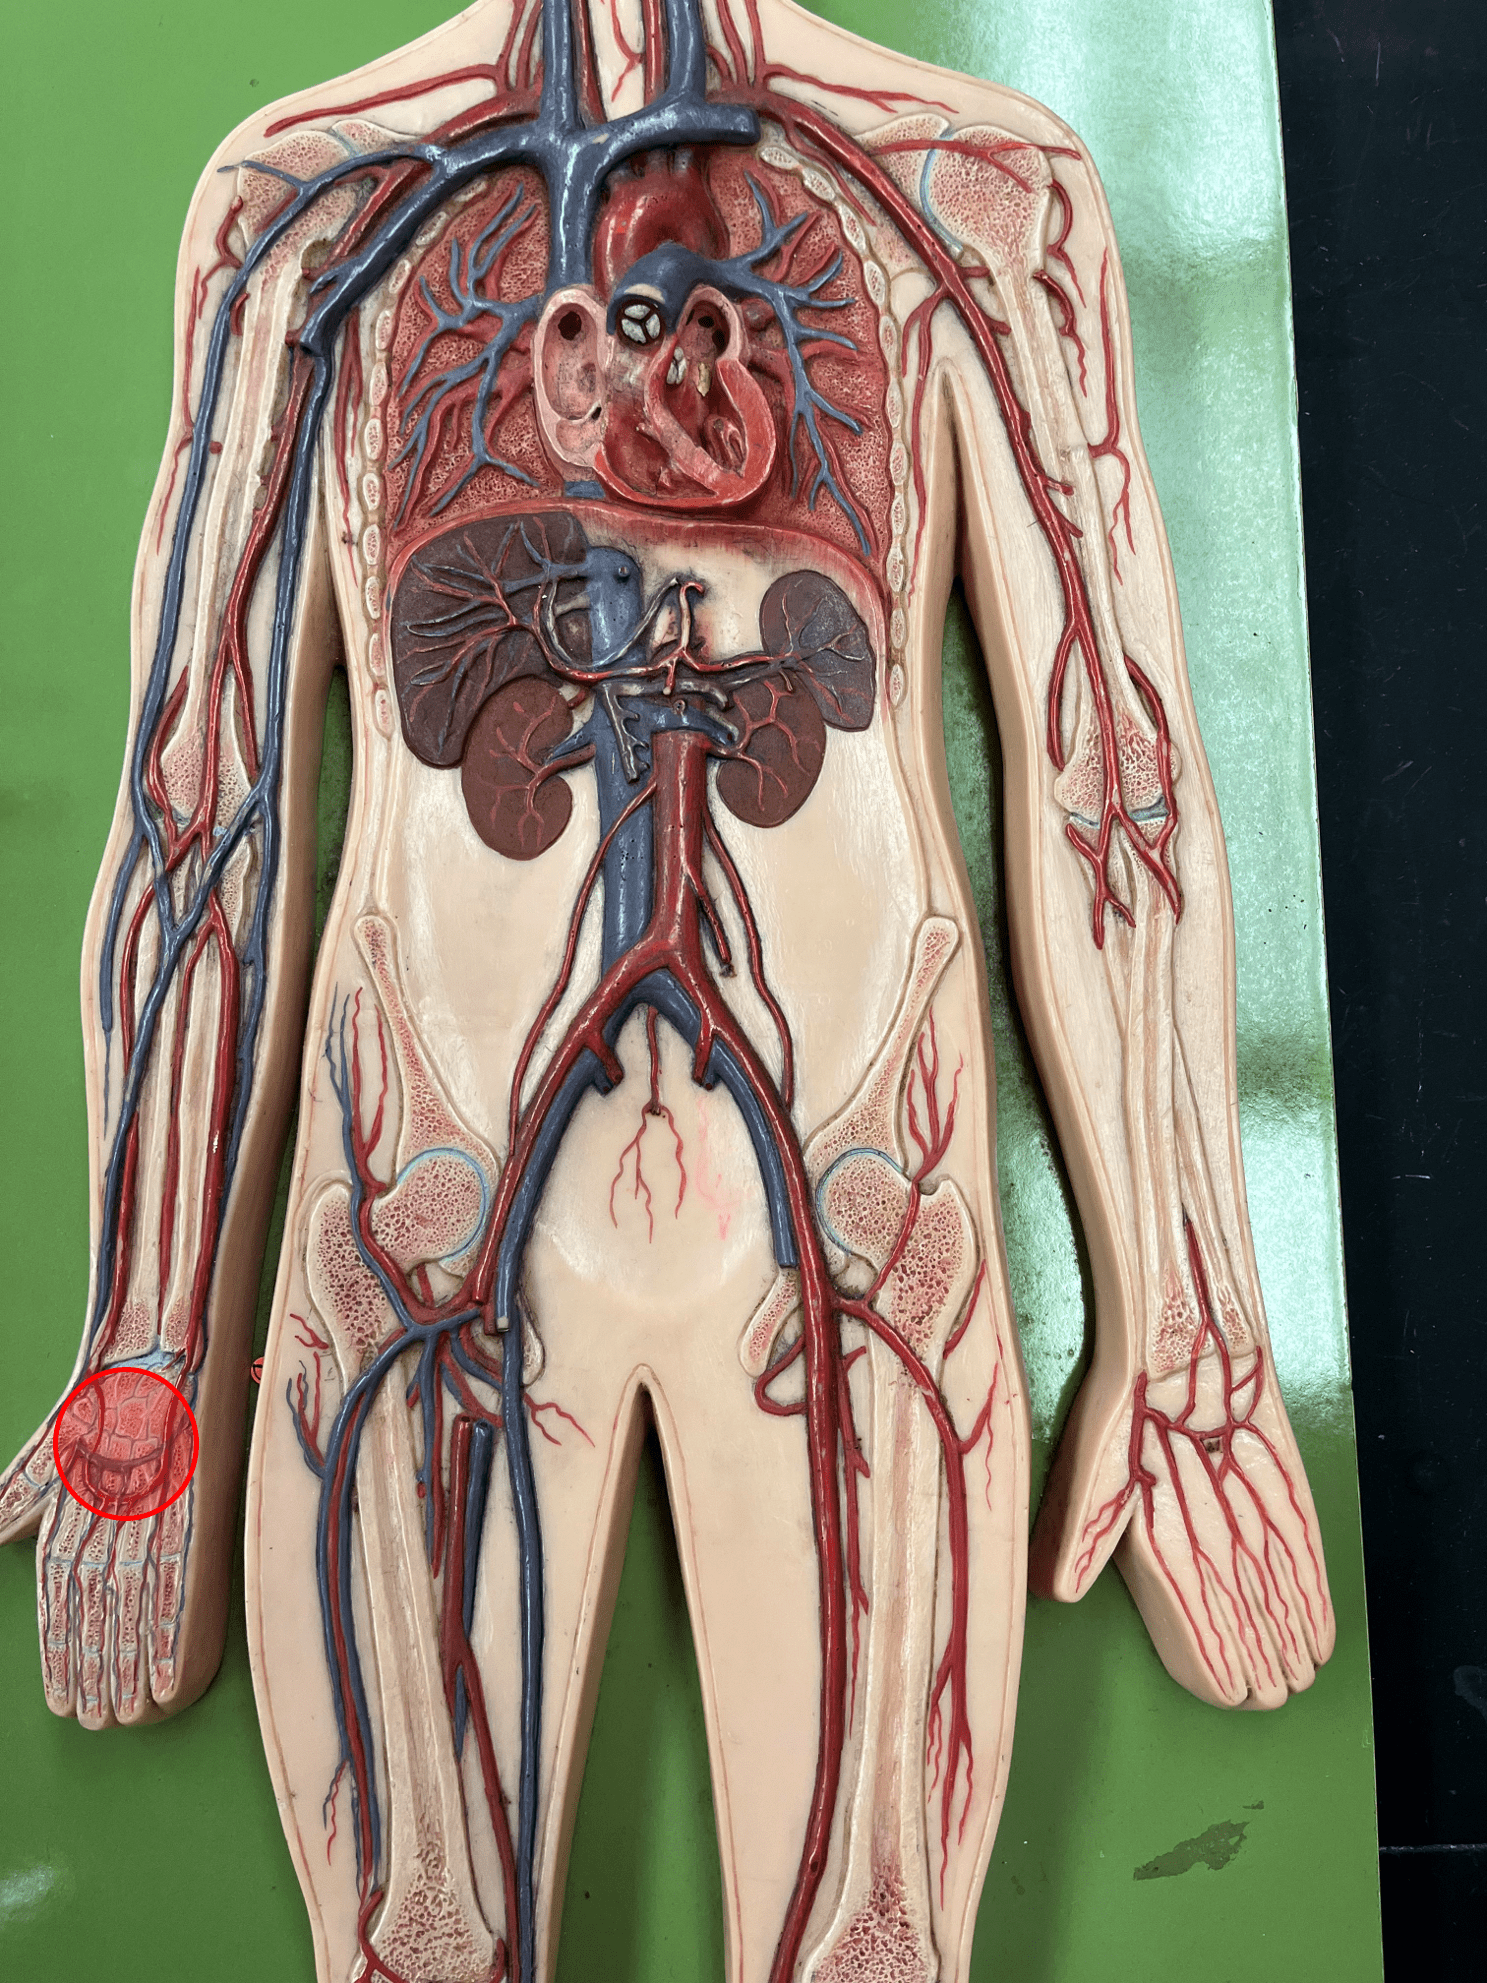

10

New cards

tunica interna

• The innermost layer of an artery.